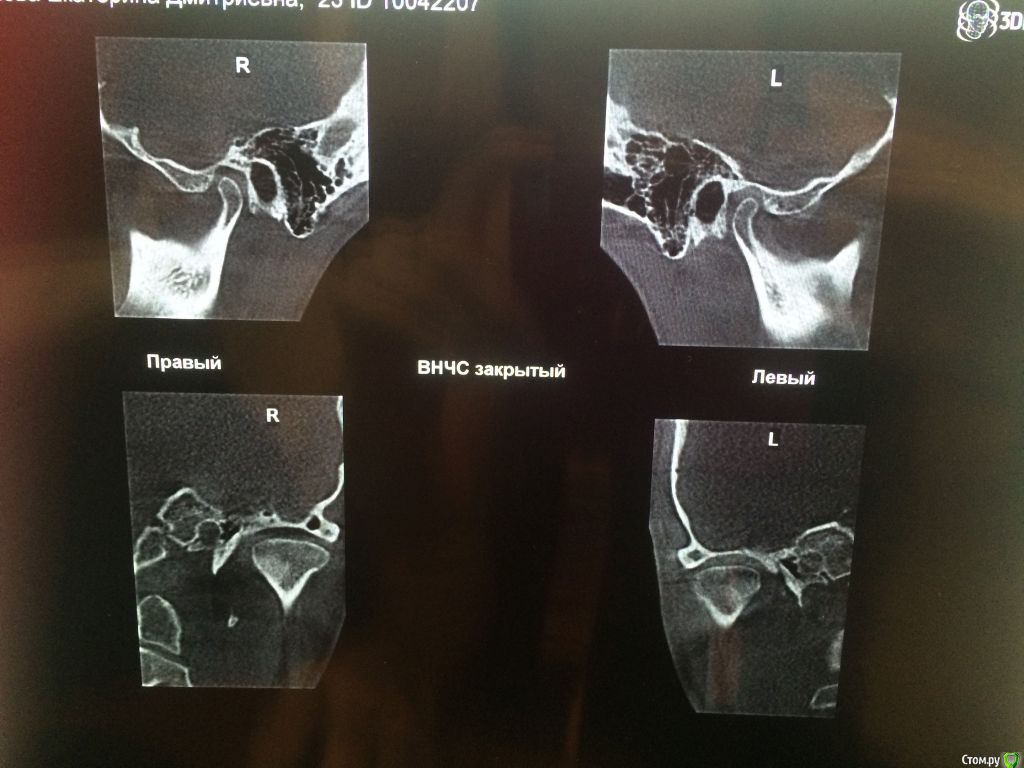

Добрый день! Очень прошу помочь с выбором врача или рекомендаций по лечению. С 2010 по 2012 год я носила брекеты (зубы были ровные, но с левой стороны верхня челюсть полностью перекрывала нижние, не было контактов, происходило стачивание). Затем с 2012 по 2016 год мне пытались исправить зубы нижней челюсти, я носила разные каппы, пластинки, то есть зубы все это время не фиксировали в определенном положении. Затем наконец в 2016-2017 году я относила полгода корректирующую каппу, которая более-менее выровняла мне нижний ряд (там была скученность). Все это время пломбы на жевательных зубах мне не меняли, они очень сильно сточились, и мне рекомендовали их заменить. Но как раз в это время у меня заболел сустав с правой стороны (на фото он соответственно слева, где и наблюдается ассиметрия). Я стала ходить по ортодонтам-ортопедам, одни говорили, что у меня все супер с прикусом, другие говорили, что клыки не под тем углом и надо снова ставить брекеты. Устав от хождений, я обратилась за диагностикой в небезызвестный центр междисдисплинарной стоматологии. Сделала там полную диагностику, по результатам которой мне предложили либо исправить брекетами клыки и поднять прикус керамическими вкладками, либо без брекетов, но тогда ставить на клыки также вкладки. Эта процедура проводится аж в три этапа и стоит как крыло самолета. Я прилагаю результаты моей диагностики. Обратилась за консультацией к другому ортопеду, который заверил, что можно обойтись временными и затем керамическими вкладками. Но помимо прикуса меня волнует ассиметрия улыбки, которая появилась в последнее время. Во-первых, я вижу невооруженным глазом, что зубы с правой стороны по высоте короче, чем с левой, то есть они меньше закрывают нижние зубы, чем с противоположной стороны, это же видно и на фото. Во-вторых, справа уголок губы при улыбке опускается как бы к низу, в отличе от левой стороны, где он идет ровно. В-третьих, с этой же правой стороны при улыбке мыщца начинается дергаться... Сейчас я уже запуталась, к какому врачу мне обращаться с данной проблемой: к ортодонту, к ортопеду, либо это гипертонус мыщц (хотя в закрытом состоянии эта ассиметрия не так заметна) Заранее благодарю за рекомендации.

Вам необходим врач-ортокраниодонт. Пытаться найти решение проблемы только на уровне зубов будет крайне трудно, да и бесполезно. Это сравнимо с симптоматическим лечением, когда идёт борьба только с симптомами заболевания, но никак не влияя на главную причину. Природа Ваших проблем (ДВНЧС, асимметрия) кроется в черепе, а точнее, в имеющимся его искажении